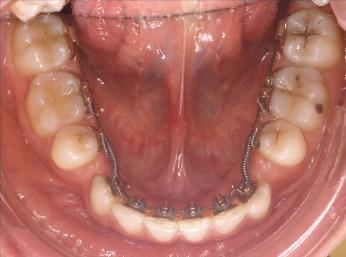

La technique linguale

Totalement invisible les attaches orthodontiques sont collées sur la face linguale